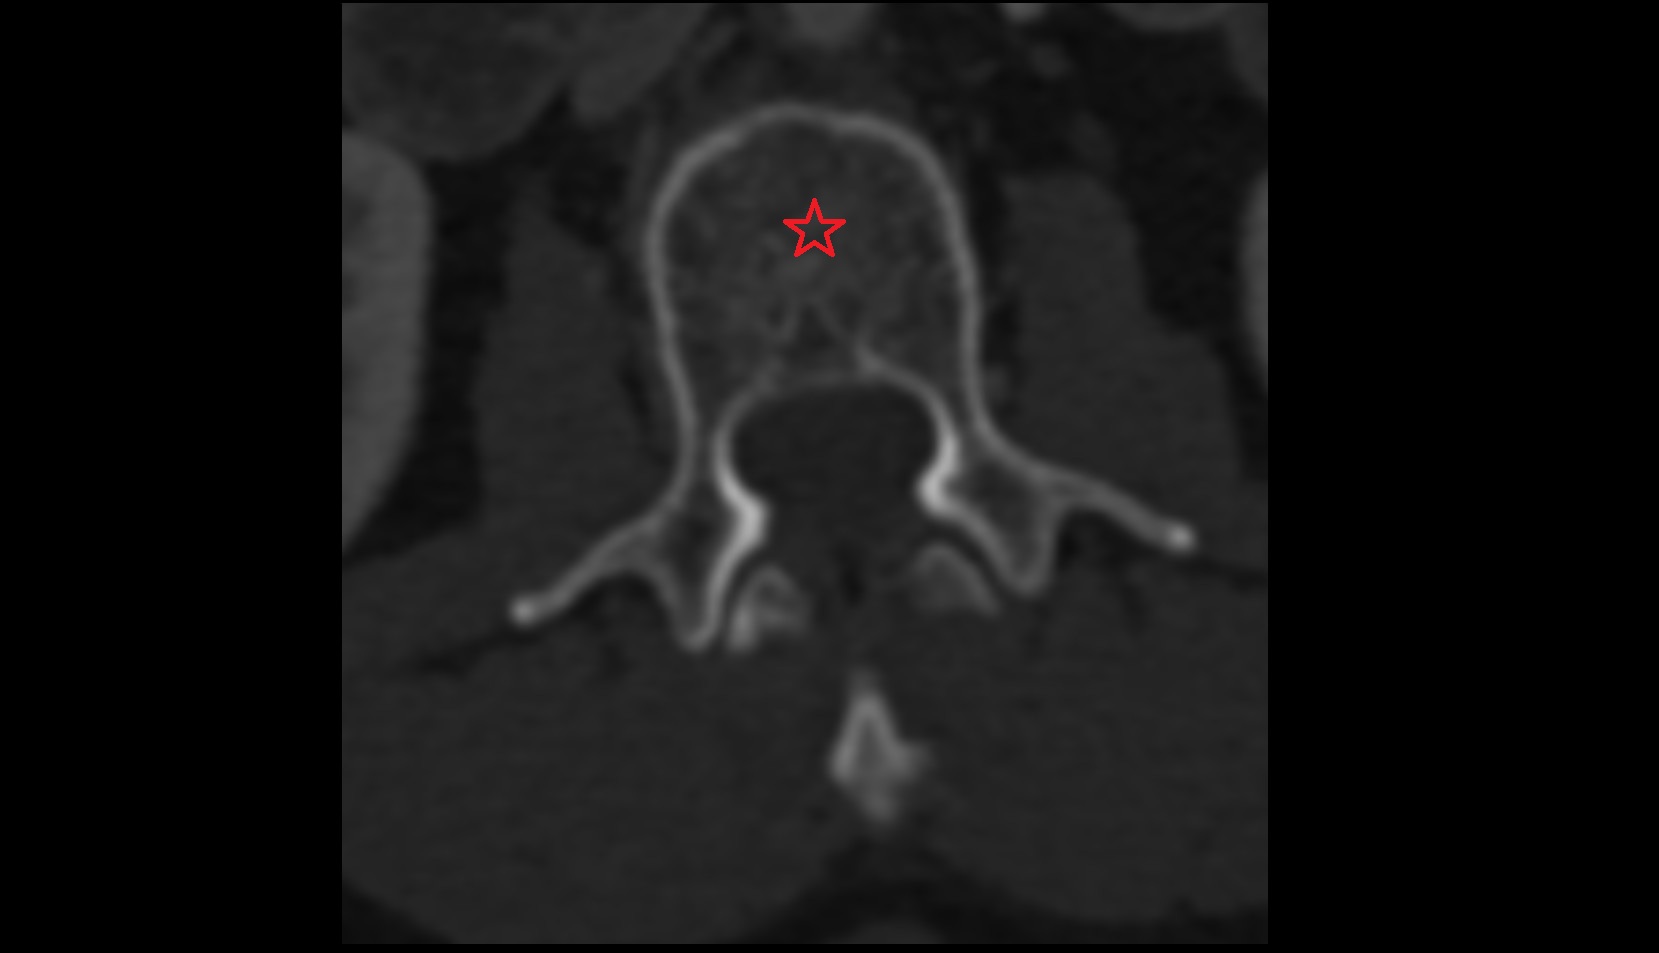

- Anulus fibrosus of intervertebral disc

- Nucleus pulposus of intervertebral disc